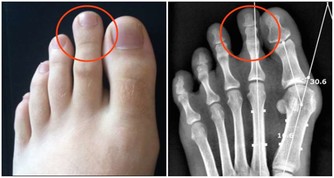

②大敦穴

大敦穴位於足厥陰肝經上,適當按壓,可以疏肝理氣、清肝明目。

取穴方法:腳拇指甲根靠近第二足趾方向,甲根邊緣向外2mm處即是。

按摩方法:找到大敦穴的位置後,雙手同時按住雙側足趾上的穴位,用力按壓約6~8秒,按壓時配合均勻緩慢地呼吸,重複按壓動作10次。